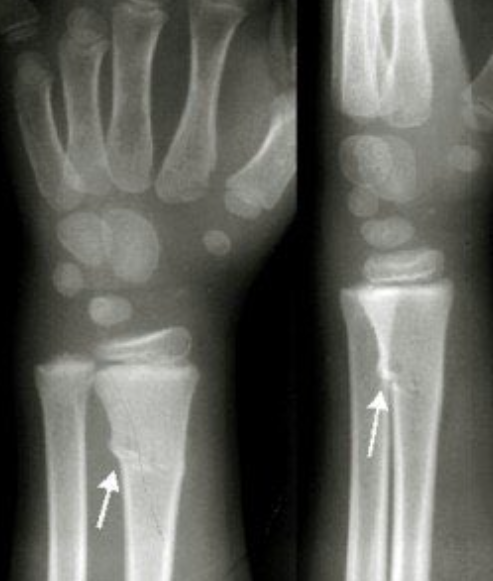

قوة التحمل الكامنة في مراكز النمو لمقاومة الإصابات هي أقل من قوة بقية العظم، لذلك قد تحصل كسور الأطفال في مراكز النمو نفسها كما هو موضح

كسور مراكز النمو تحتاج إلى عناية خاصة من قبل الطبيب المعالج ومتابعات على مدى بعيد للتأكد من سلامتها وعدم تأثرها من الإصابة...

قد تتسبب كسور مراكز النمو بضرر كامل او جزئي في مركز النمو.

إذا تضرر كامل مركز النمو سينتج عن ذلك توقف للنمو في العظمة المصابة مما سيتسبب في قصر متزايد في العظمة المصابة بالمقارنة مع الطرف السليم الذي يكمل نموه بالمعدل الطبيعي. الفارق النهائي يعتمد على عمر الطفل وقت الإصابة

في حال كان الضرر في مركز النمو جزئيا، فالجزء المتبقي من مركز النو سيتسبب بنمو غير متماثل في العظمة ينحرف بها عن استقامتها الطبيعية.

لذلك كسور مراكز النمو تحتاج عناية ومتابعة متخصصة.